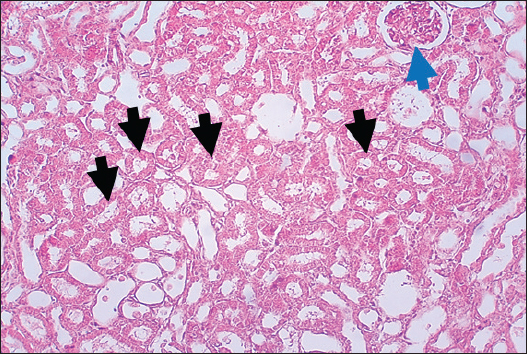

In the control group, histological analysis of kidney sections revealed intact glomeruli and renal tubules (Fig. 1). Conversely, Figure 2 presents a kidney section from the green tea group, which exhibited normal renal tubular epithelial cells, a well-preserved tubular lumen, and an overall normal tubular texture, although some glomeruli showed mild atrophy. The renal section of gentamicin showed atrophy of the glomerular tuft, expansion of the globular space, and significant hyperemia lesions in some glomeruli associated with substantial damage to the superficial cell layer (epithelial cells) in the proximal renal tubules, resulting in a reduction of the tubular lumen space (Fig. 3). In contrast, kidney sections from the gentamicin group that received green tea treatment revealed a marked reveal of both glomeruli and renal tubular epithelium, which appeared normal (Fig. 4 and Fig. 5).

Fig. 1. Rat Kidneys of control rat. The section shows the normal texture of renal tissue (glomeruli, Black arrows) and renal proximal tubules (Red arrows) without any significant occupied lesion. H and E (10X).